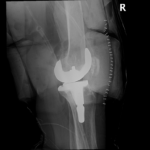

Your doctor will diagnose osteoarthritis based on the medical history, physical examination, and X-rays.

X-rays typically show a narrowing of the joint space in the arthritic knee.

The surgery is performed under spinal or general anesthesia. Your surgeon will make an incision in the skin over the affected knee to expose the knee joint. Then the damaged portions of the femur bone are cut at appropriate angles using specialized jigs. The femoral component is attached to the end of the femur with or without bone cement. The surgeon then cuts or shaves the damaged area of the tibia (shinbone) and the cartilage. This removes the deformed part of the bone and any bony growths, as well as creates a smooth surface on which the implants can be attached. Next, the tibial component is secured to the end of the bone with bone cement or screws. Your surgeon will place a plastic piece called an articular surface between the implants to provide a smooth gliding surface for movement. This plastic insert will support the body’s weight and allow the femur to move over the tibia, similar to the original meniscus cartilage. The femur and the tibia with the new components are then put together to form the new knee joint. To make sure the patella (knee cap) glides smoothly over the new artificial knee, its rear surface is also prepared to receive a plastic component. With all the new components in place, the knee joint is tested through its range of motion. The entire joint is then irrigated and cleaned with a sterile solution. The incision is carefully closed, drains are inserted and a sterile dressing is placed over the incision.